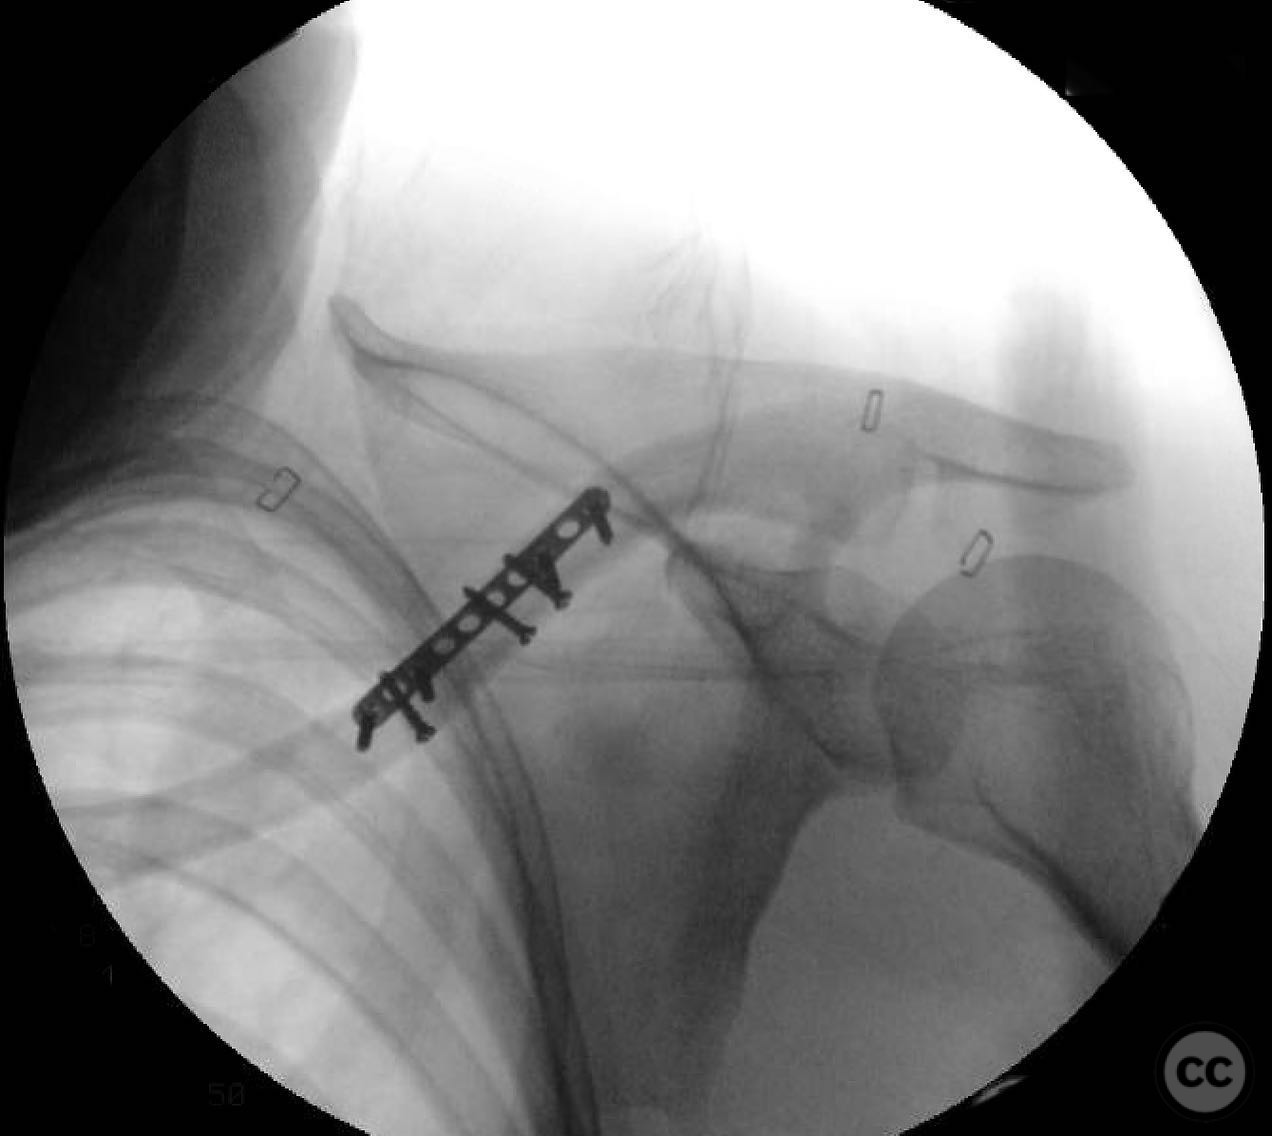

During the procedure, anatomic reduction of the butterfly fragments was achieved using 2.4mm lag screws for interfragmentary compression. The main segment reduction proved challenging due to instability; hence, a 2.4mm "clamp replacement plate" was temporarily used to maintain reduction. A reconstruction plate was contoured and applied to the anterior inferior clavicle, providing a neutralization construct. Absolute stability was achieved, anticipating primary bone healing.

Orthopaedic implants used:   2.4mm lag screws, 2.4mm clamp replacement plate, reconstruction plate.